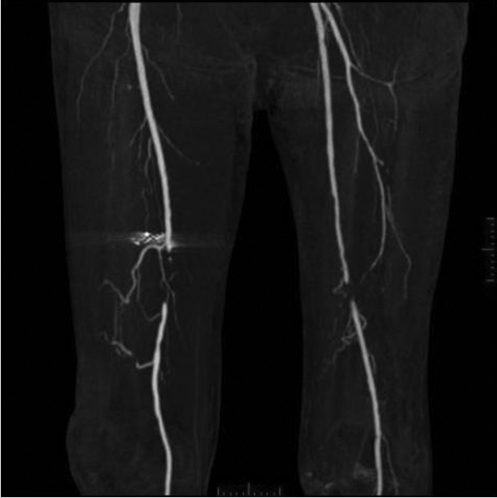

After the decision is made to reconstruct the lower extremity, the first preoperative evaluation should start with vascular status. Without adequate vascular supply, microsurgical reconstruction will not be possible. This is especially true for ischemic conditions after trauma and ischemic chronic wounds. Most often, physical examination of palpable pulse, color, capillary refill, and turgor of the extremity allows us to assess the initial status. With the handheld Doppler examination, further information can be obtained.7 The use of preoperative arteriography for lower extremity reconstruction is considered when physical/Doppler examination reveals inconclusive vascular status or chronic vascular disease is suspected. It is usually performed for patients who have loss of one or more peripheral pulses, a neurologic deficit secondary to the injury, or a compound fracture of the extremity that has undergone reduction and either external or internal fixation.8 In association with prior injuries to the lower extremity, the routine preoperative use of angiogram is controversial.7,8,9,10,11,12,13 However, in our experience, 75 to 80% of lower extremity reconstruction that involves trauma, chronic wounds, and oncologic reconstruction may be indicated for detailed vascular evaluation. If angiogram is required, the simpler way is to obtain the vascular status by computed tomography (CT) angiography of the recipient region without the risk of complications from arterial puncture of the groin. In addition, it can provide vascular information of the donor flap when selected from the extremity, facilitating the planning and the surgical procedure.11,14,15▶ Fig. 9.1 shows a patient with a diabetic foot having obstruction of both femoral artery and distal circulation being supplied by collateral vessels. This patient exhibited normal handheld Doppler findings and thus justifies the angiogram in patients with chronic conditions such as diabetes. It also shows the quality of the artery whether or not it is calcified proximal to the lesion, which may warrant angioplasty to improve distal flow. This can be frequently seen in patients with diabetes or other peripheral artery disease. Furthermore, it shows you whether or not calcification is present on the recipient artery, thus helping you to decide on selection of the artery near the defect. Finally, the CT angiogram when programed can see though the venous phase, detecting the superficial veins and the presence of deep vein thrombosis. However, in the cases where hardware is applied, it may distort the image. In these cases, although more invasive, classical angiogram will help the surgeon to determine the vascular status.

Fig. 9.1 A patient with a diabetic foot having obstruction of both femoral artery and distal circulation being supplied by collateral vessels. This patient exhibited normal hand-held Doppler findings and thus justifies the angiogram in patients with chronic condition such as diabetes. If one would harvest the anterolateral thigh flap without this knowledge, it would be catastrophic for the limb circulation as the major collateral vessel is the descending branch of the lateral circumflex femoral artery.